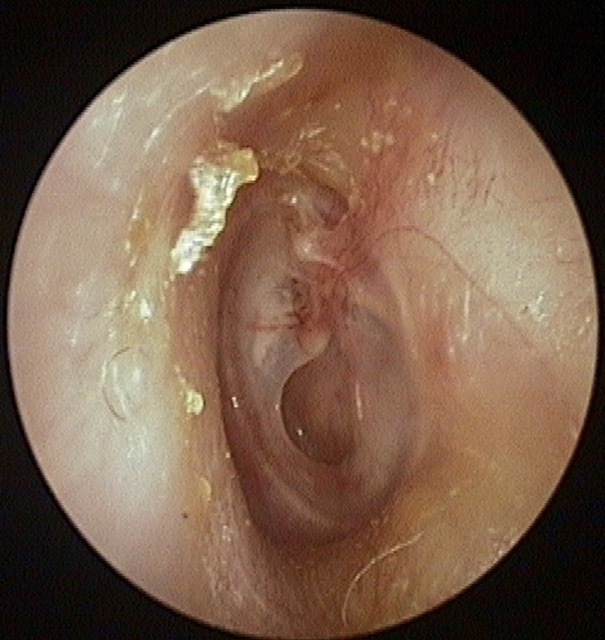

Perforation